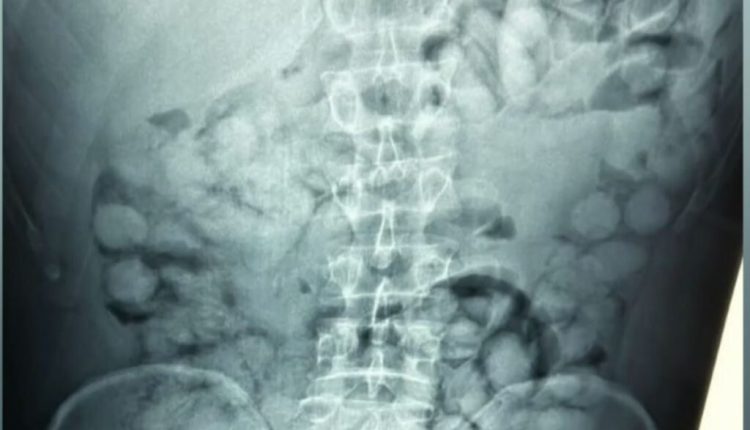

Στις ακτινογραφίες διακρίνονται οι συσκευασίες που είχε καταπιεί με τους γιατρούς να εντοπίζουν 100 κάψουλες των 11 γραμμαρίων η καθεμία.

Η συγκεκριμένη μέθοδος διακίνησης ναρκωτικών είναι εξαιρετικά επικίνδυνη, αφού αν άνοιγε στο στομάχι του έστω και μία συσκευασία, σε λίγα λεπτά θα είχε πεθάνει. Σύμφωνα με τις πρώτες πληροφορίες, η συνολική ποσότητα κοκαΐνης που εντοπίστηκε ξεπερνάει το ένα κιλό. Η έρευνα των αρχών συνεχίζεται για τον εντοπισμό και άλλων εμπλεκομένων στην υπόθεση.